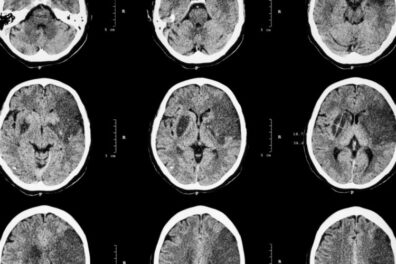

Ювенильный инсульт